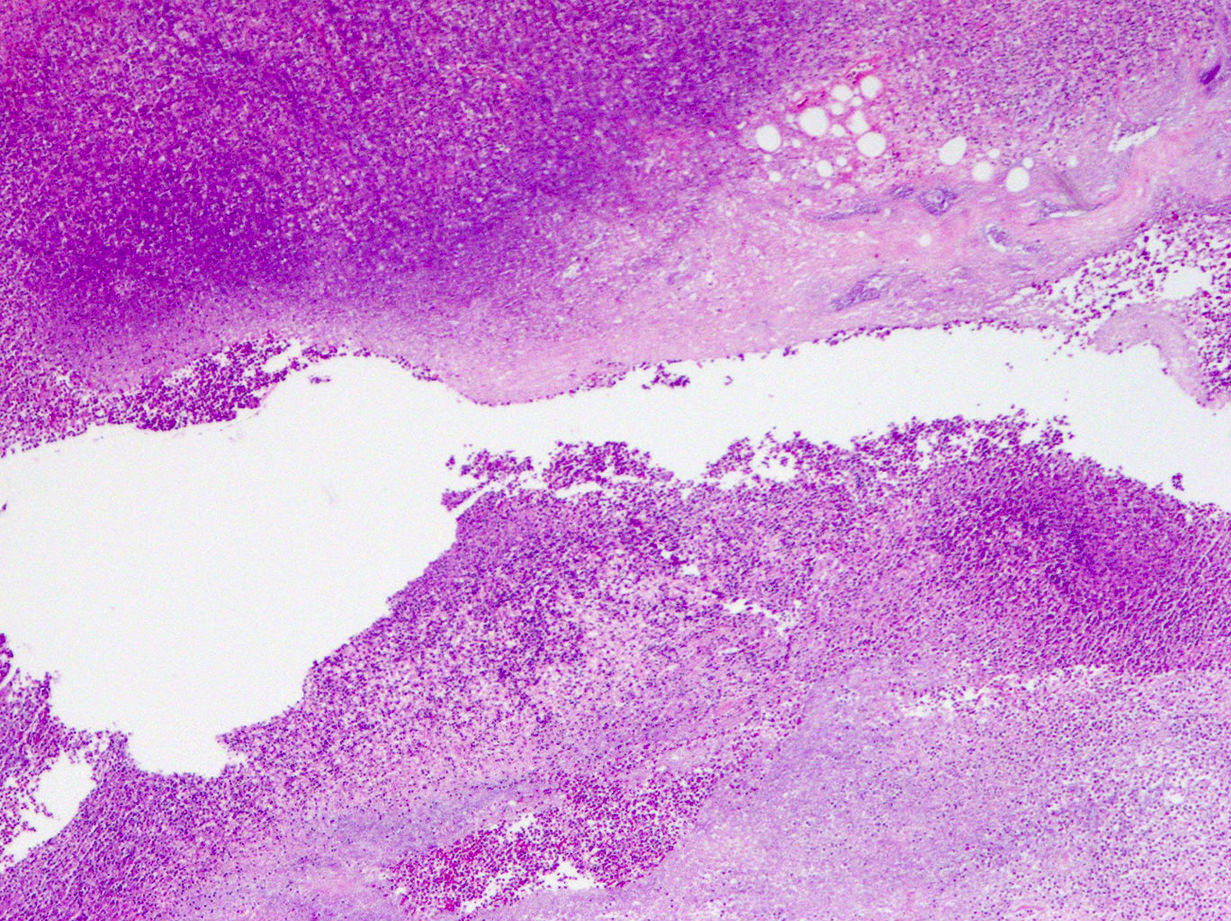

Microscopic (histologic) description

- Variable acute inflammation with predominance of neutrophils; involves some or all layers of the appendiceal wall

- Process may be divided into acute focal, acute suppurative, gangrenous and perforative

- Early lesions display mucosal erosions and scattered crypt abscesses

- Later, the inflammation extends into the lamina propria and collections of neutrophils are also seen in the lumen

- Mural necrosis in gangrenous appendicitis

- Process may be divided into acute focal, acute suppurative, gangrenous and perforative

Microscopic (histologic) images

A 40 year old caucasian man presented into the emergency room with right lower quadrant pain associated with vomiting, abdominal tenderness, fever and moderate leukocytosis. Acute appendicitis was suspected and he underwent an appendectomy. His appendix was sent to pathology for histological evaluation. The H&E images are shown above. Which of the following is the most likely diagnosis?